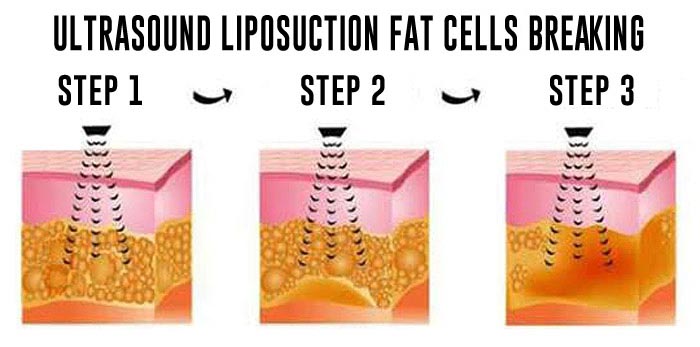

The apparatus therapeutic effect is based on thermal effects enabling focused ultrasound waves to precisely target tissue and the depth NOT impairing any structures through which they travel. Transformation of HIFU waves energies into thermal energies achieves therapeutic effects which are exclusively NON-ABLATIVE and BIOSTIMULATIVE enabling the treatment to stimulateneosynthesis of collagen and its regeneration and reorganisation. It also encourages neovascularization of the treated area.

In recent years HIFU technology has been successfully applied in treatments of vaginal relaxation (VRS) and stress incontinence (SUI). Precise application of HIFU waves to vaginal walls at a depth of 3 to 4.5mm warms submucosa and mucous membrane to 65⁰C. This method practically instigates connective tissue of mucous membrane to regenerate. The treatment results in higher numbers of stronger, remodeled and narrowed collagen fibers which permeate and provide strength of vaginal walls. In addition, biostimulative effects of HIFU wave initiated regenerative processes have positive impacts on the elastic fibers of mucosa and pelvic muscles. Final results of the treatment are reflected by a narrowed vaginal canal with stronger, more resistant and healthier walls. All these effects are beneficial in the treatment of SUI hence why HIFU is also applied in treatments of first and second degree SUI whilst third degree SUI requires surgery. HIFU application in treatment of first and second degree SUI can significantly delay the development of third degree SUI and therefore delay or completely eliminate the need for surgical treatment.